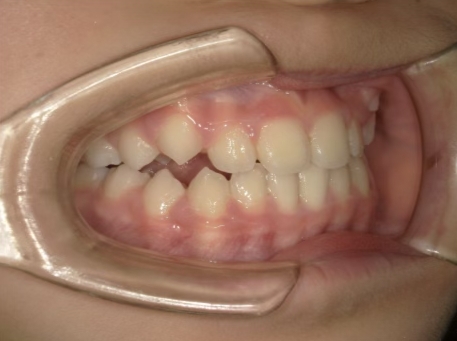

治療前① 小1:6y8m 初診

| カウンセリング・診断結果 | 前歯の生え変わり時期に来院されました。(写真①) 乳歯列期に受け口の既往があり切端咬合になりそうなため、受け口に対する矯正治療の考え方と対処法、当院のコンセプトを説明したところ治療を希望されたので診断を行いました。 診断の結果、上顎骨に対し下顎骨が長く、骨格的な構造も下顎突出型反対咬合(下顎骨が適切な位置よりも前に出ているタイプの受け口)と分かりました。 顔立ちは、中顔面が引っ込んだように見えるコンケーブに移行中です。 機能的な問題として低位舌があるため受け口の悪化が考えられることも説明し、以下の治療を提案しました。 |